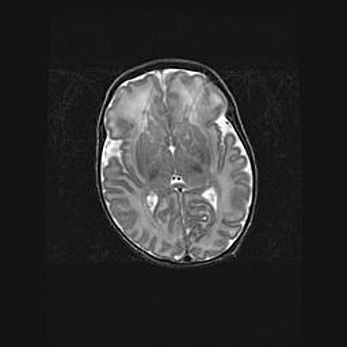

Сообщающаяся гидроцефалия. Кистозная энцефаломаляция головного мозга.

Возраст: 3 месяца 4 дня

Вес: 3100 г

Пол: женский

Окружность головы: 34 см

Срок гестации: 31 неделя

Кистозная энцефаломаляция головного мозга - одна из форм поражения головного мозга в детском возрасте. Характеризуется возникновением множественных и распространённых кист в коре, белом веществе и подкорковых образованиях головного мозга у плодов, новорождённых и детей раннего возраста. Развитие кистозной энцефаломаляции связано с внутриутробной асфиксией и гипотонией, родовой травмой, тромбозом синусов, пороками развития сосудов, инфекциями, сепсисом и другими причинами. Наиболее значимые инфекционные агенты: вирусы простого герпеса, цитомегалии, краснухи, токсоплазмы, энтеробактерии, золотистый стафилококк и другие.